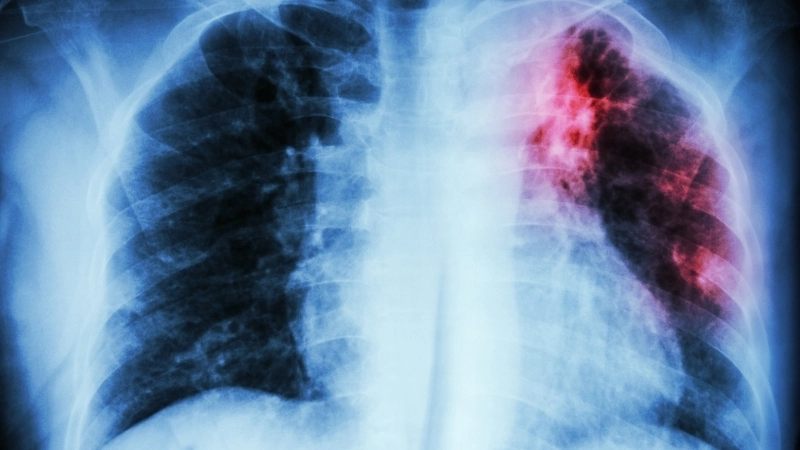

Hình ảnh x quang lao phổi điển hình